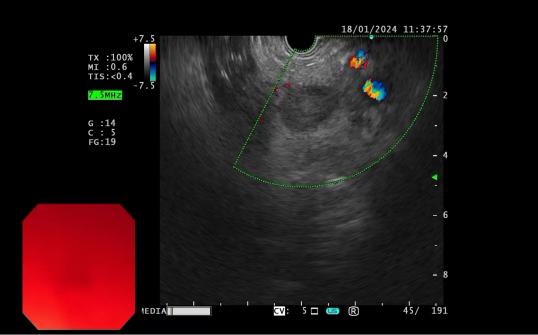

發現內源性低回聲病灶        實時超聲引導下對病灶的細針穿刺活檢

內鏡超聲引導下細針穿刺抽吸術(EUS-FNA):治療對于性質不明的胰腺實性占位性病變;對于經CTMRI或 EUS 等檢查不能確定性質的胰腺囊性病變;對于消化道毗鄰組織中性質不明的占位性病變或淋巴結腫大(如縱隔、上腹部等部位病變);長徑>2cm需要手術切除但具有高手術切除風險,或不能切除的消化道上皮下腫瘤的鑒別診斷。